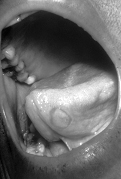

Mucous patches form during the breakdown of mucous membranes, seen here on the inferior surface of the tongue. During the secondary stage of syphilis, mucous patches can also develop inside the mouth, vulva, and vagina.

A photograph of mucous patches on the tongue due to secondary syphilis.

Photo Credit: CDC/ Susan Lindsley

This image depicts a lingual mucous patch on the tongue of a patient who was subsequently diagnosed with secondary syphilis.